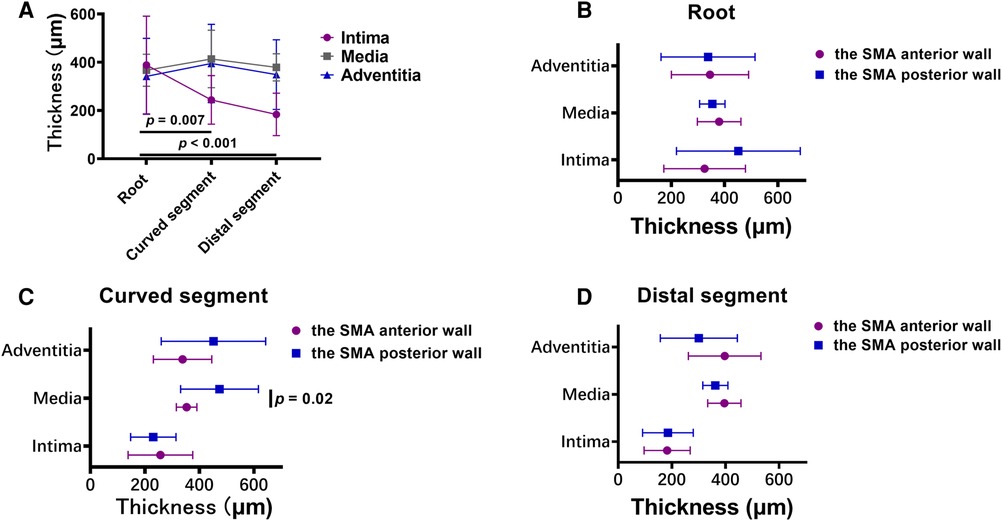

The mean thickness of the intima at the root of the SMA (388.5 ± 202.3 µm) was greater than that in the curved (243.8 ± 100.5 µm; p = .007) and distal (183.7 ± 88.0 µm; p < .001) segments. However, there was no significant difference in the mean thickness of the other 2 layers across the 3 locations of the SMA. In the curved segment of the SMA, the mean thicknesses of the intima (256.8 ± 118.4 µm), media (353.1 ± 37.6 µm), and adventitia (338.2 ± 107.2 µm) at the anterior wall were lower than the mean thicknesses of the intima (230.7 ± 83.2 µm; p = .58), media (473.7 ± 142.8 µm; p = .02), and adventitia (451.4 ± 191.8 µm; p = .12) at the posterior wall. There was no significant difference between the anterior and posterior walls in the mean thicknesses of the 3 layers at the other 2 locations of the SMA (Figures 6A–D).

Figure 6. (A) broken-line graphs of the mean value of the thickness of each layer of the vascular wall in the three superior mesenteric artery (SMA) segments. (B–D) The thickness of each layer of the vascular wall in the root (B), curved segment (C), and distal segment (D) of the SMA.